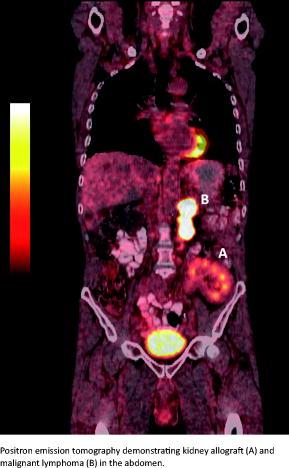

Acknowledgement: We would like to extend our thanks to Henrik Andersen, for translation and proofreading. The picture was kindly provided by Anne Lerberg Nielsen, Department of Nuclear Medicine, Odense University Hospital.